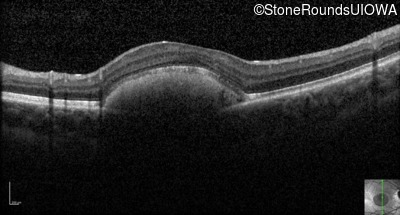

Visit at age: 16 years

Optical Coherence Tomography - Left - 20/30 sc

Exemplar / OCT Stack